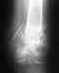

Re: Задний вывих головки плечевой кости?

Еще раз. Ответ о наличии вывиха и целесообразности операции был дан. Дальнейшее углубление в детали не решит главной проблемы - отсутствия на месте необходимого уровня медпомощи. Никакой "теоритической" помощи не существует. Есть смысл "сыпать бисер" профессиональной информации перед тем, кто ей может профессионально распорядиться.